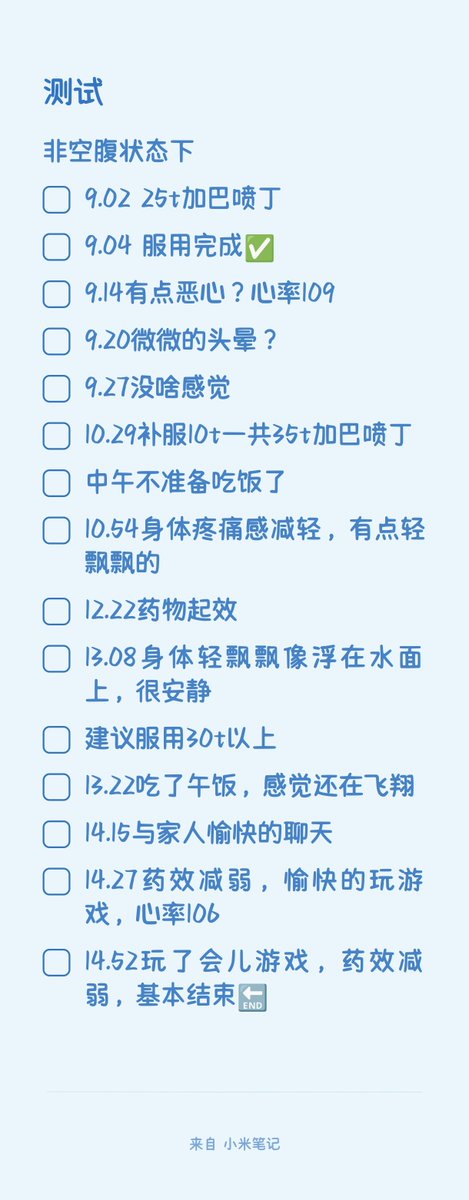

2024-08-14 11:34:53 UTC

甚至在第二天有余晖的感觉,虽然发生了很多破事但没怎么影响心情*抗焦虑&镇静

运动协调性稍差,表现为走路和站立时平衡不好

此剂量下对睡眠的改善作用,增加了慢波睡眠且没有影响rem,精力恢复+

FDA数据,在临床剂量下(75-600mg)普瑞巴林的依赖性低于bzd,并相比之下它产生的认知和精神运动障碍较轻 https://t.co/TJ7ZOQ7pbC